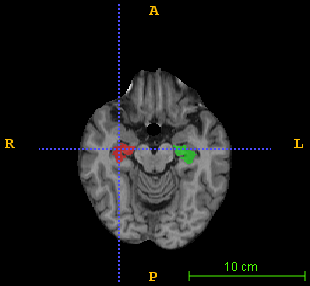

Over the past decades, state-of-the-art medical image segmentation has heavily rested on signal processing paradigms, most notably registration-based label propagation and pair-wise patch comparison, which are generally slow despite a high segmentation accuracy. In recent years, deep learning has revolutionalized computer vision with many practices outperforming prior art, in particular the convolutional neural network (CNN) studies on image classification. Deep CNN has also started being applied to medical image segmentation lately, but generally involves long training and demanding memory requirements, achieving limited success. We propose a patch-based deep learning framework based on a revisit to the classic neural network model with substantial modernization, including the use of Rectified Linear Unit (ReLU) activation, dropout layers, 2.5D tri-planar patch multi-pathway settings. In a test application to hippocampus segmentation using 100 brain MR images from the ADNI database, our approach significantly outperformed prior art in terms of both segmentation accuracy and speed: scoring a median Dice score up to 90.98% on a near real-time performance (<1s).